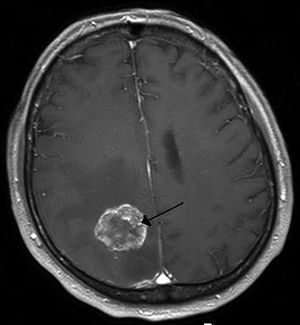

| Brain metastasis in the right cerebral hemisphere from lung cancer shown on T1-weighted magnetic resonance imaging with intravenous contrast. (L=left, P=posterior, back of the head) | |

سرطان الدماغ Brain Tumor، هو إنقسام غير طبيعي وغير منتظم لخلايا الدماغ سواء في المخ أو المخيخ أو الحبل الشوكي والذي يسبب إنضغاط لأجزاء الدماغ الأخرى و بالتالي فقدان لإحدى الوظائف أو ضعفها.

وأورام الدماغ الأولية (أي التي منشأها الأصلي الدماغ) نادرة جداً، بعكس أورام الدماغ الثانوية التي تكون ناتجة عن إنتشار الورم من أعضاء أخرى بالجسم وصولاً إلى الدماغ.